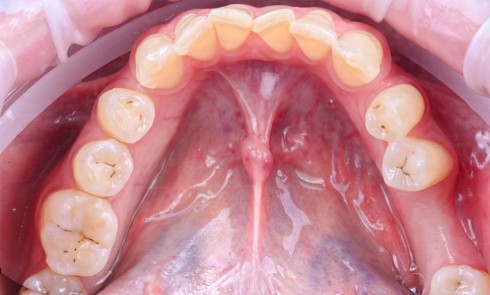

Actes préopératoires

La couronne a été déposée et une vis de couverture mise en place. La patiente a reçu un nettoyage supra-gingival général avec une attention particulière pour l’implant 47, et une irrigation locale avec du gel de chlorhexidine et du peroxyde d’hydrogène pour réduire l’inflammation des tissus. De l’amoxicilline (3 x 500 mg) a été prescrite, à commencer la veille de l’intervention chirurgicale.